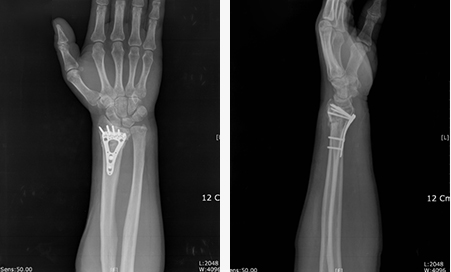

그래서 KS병원의 현재 치료방법은 수술용 금속판으로 견고하게

고정하고 조기 재활을 하여 후유증 없이 일상생활에 일찍 복귀

할 수 있도록 치료하고 있습니다.

수술 후